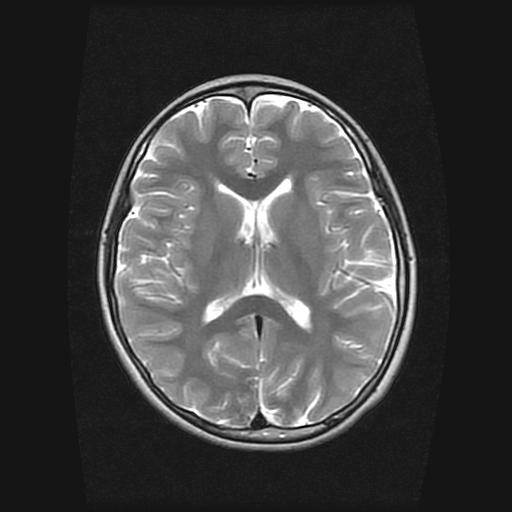

9岁女孩,三岁时诊断为癫痫,一直服丙戊酸钠,现患者一般情况良好,家长复查核磁片,看能否停药..

巨脑回

未见异常信号灶.

停药要结合临床,如无发作可以停。